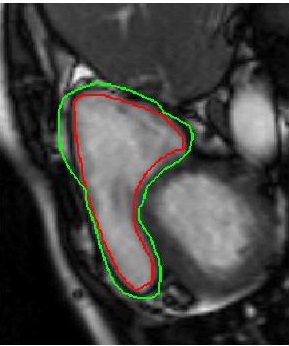

Table 2 summarizes the performance of different methods, and Figure 3 shows superimposed manual contour of the RV (red) and the deformed contour of the registered image (green). Better registration is reflected by closer alignment of the two contours. Once again it is obvious that has the best performance amongst all competing methods, and its advantages over when including deformation consistency.

![]() |

| (a) | (b) | (c) | (d) |